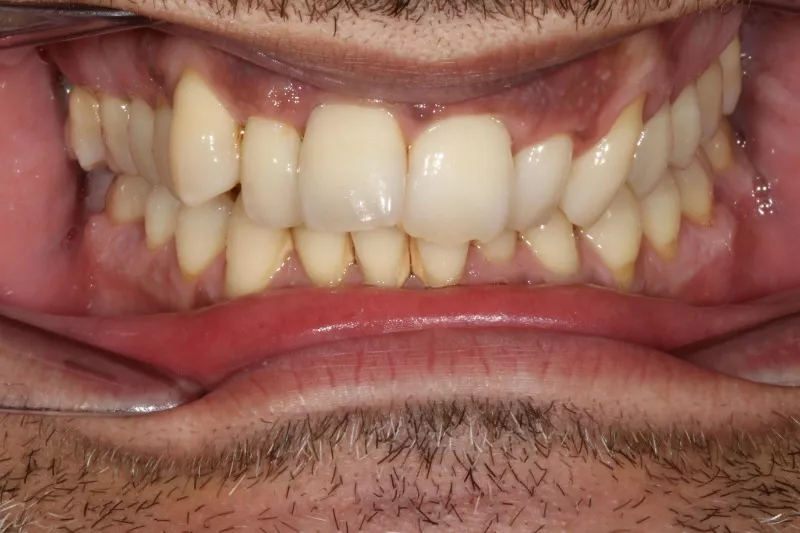

Upper Arch Invisalign to fix overcrowded teeth